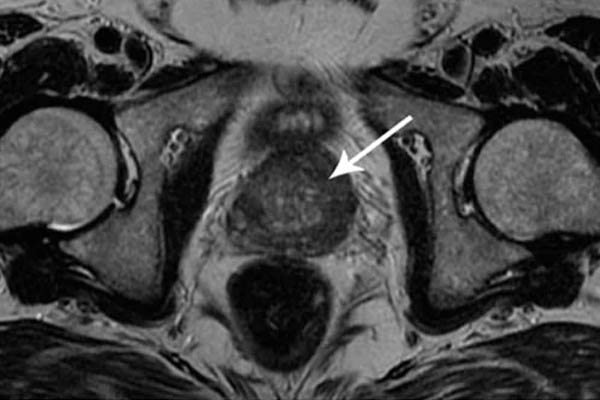

Saya ingin menunjukkan beberapa foto tentang apa yang terjadi pada sistem genitourinari dan organ dalam lainnya dari seorang pria ketika dia berhenti berhubungan seks.

Seperti inilah peradangan prostat karena stagnasi di dalamnya (dengan tidak adanya pengosongan testis, yang terjadi saat berhubungan seks). Peradangan yang berkepanjangan pertama-tama mengarah ke adenoma, dan kemudian ke kanker prostat (dari mana, menurut statistik, 38% pria meninggal). Dengan tidak adanya seks, ini selalu terjadi, itulah sebabnya adenoma dianggap sebagai penyakit orang tua.

Kanker prostat. Ini didiagnosis pada seorang pria berusia 58 tahun. Alasannya adalah penahanan nafsu dalam jangka panjang (dari usia 51). Pria itu meninggal.